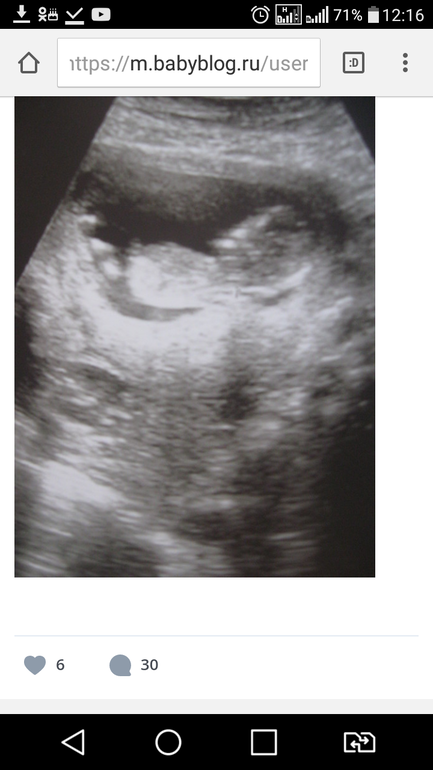

Да я если честно не видела на экране, фото именно как у всех с бугорками...Мне только показали нижнее фото где якобы вид ножек и попы

Спасибо...Я просто сижу рассматриваю фото с ножка и пытаюсь понять куда ж именно смотреть)))я ж не специалист)))

У нас я так понимаю половая пренадлежность это второе фото...

Хотя точно не знаю...

Да я тут просто в смятении от того,что на сроке 11-12 недели снизу они тоже практически одинаково выглядят)))))))))Да ещё и пуповина бывает)))